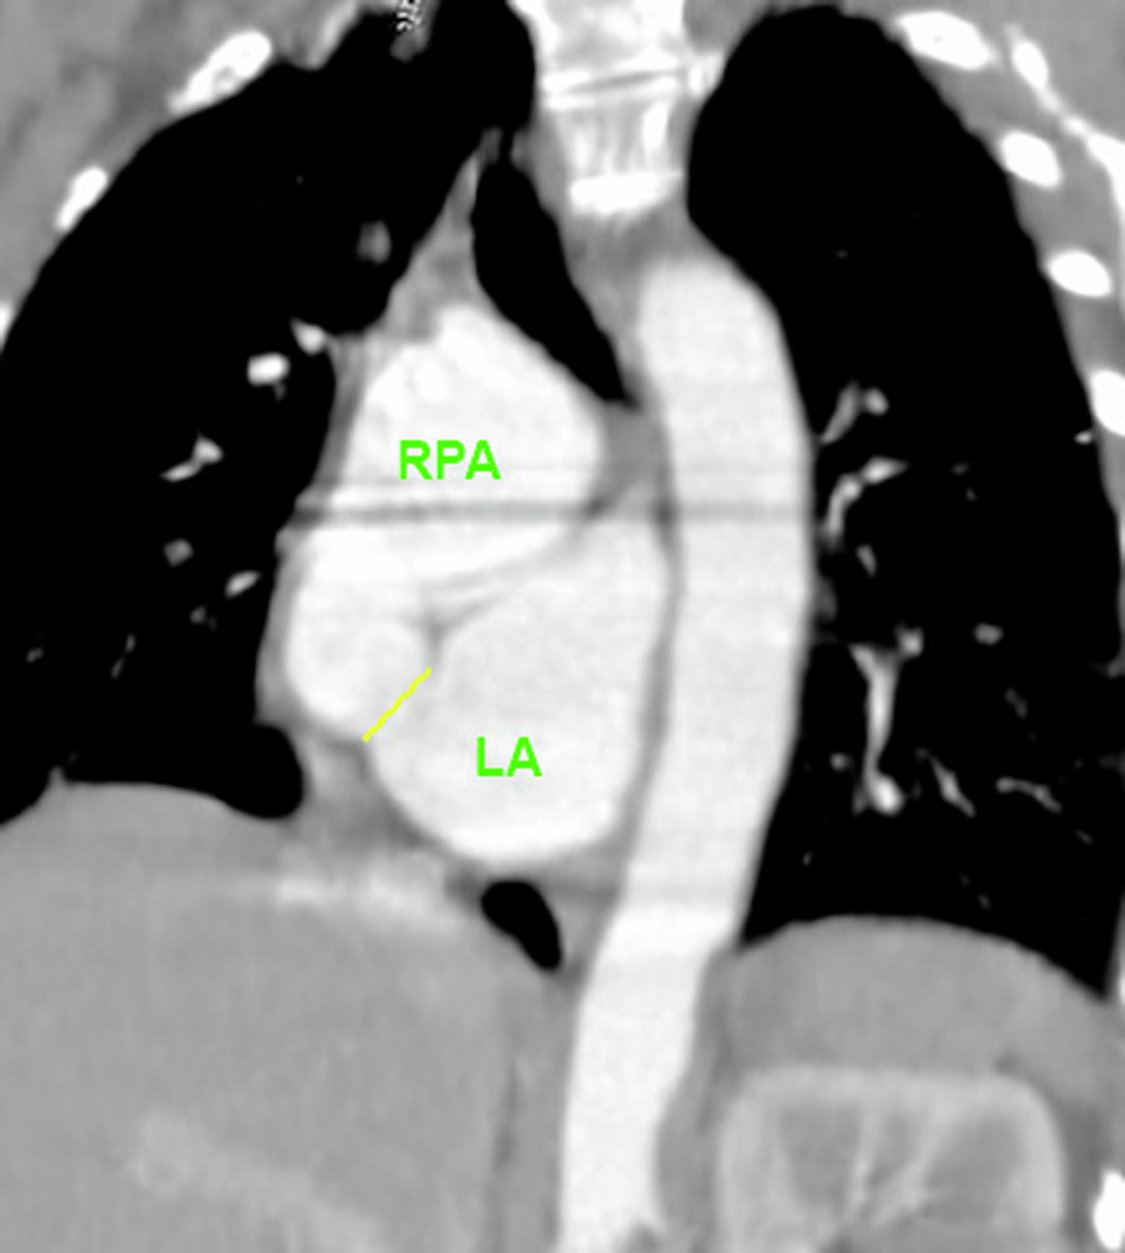

Her trans-thoracic echocardiogram demonstrated a severely dilated left atrium and residual left-to-right shunting across her interatrial septum by colour Doppler. A cardiac CT and MRI were subsequently performed for anatomical delineation of the shunt that demonstrated a severely dilated right pulmonary artery and a communication between the distal right pulmonary artery and left atrium as the distal right pulmonary artery courses inferior over the atrial mass. (Figure 1) The calculated Qp:Qs on cardiac MRI was 1.14.

Figure 1. Cardiac CT was used for pre-procedural guidance and delineates the location of the RPA-LA communication (represented by the yellow line). The cardiac CT was then used to create a 3D reconstruction using virtual reality for segmentation. Notably, the 3D reconstruction using the cardiac CT dataset overestimated the size of the communication between the RPA and LA.